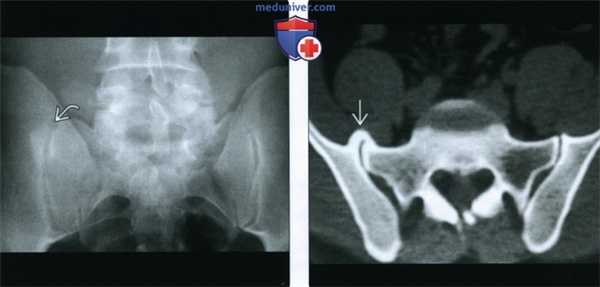

(Слева) Рентгенография в ПЗ проекции: склеротическое «повреждение» на уровне верхней части правого крестцово-подвздошного сустава. Важно помнить, что ОА крестцово-подвздошных суставов может проявляться либо диффузным склерозом кортикального слоя, либо в виде округлых участков склероза в верхней или нижней части синовиальной порции сустава.

(Справа) КТ, аксиальная проекция, костный режим: у этого же пациента подтверждается наличие очага склероза, представленного типичным краевым остеофитом, перекрывающим крестцово-подвздошный сустав.